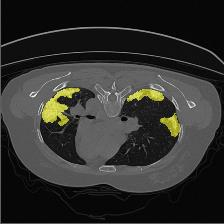

Medical image segmentation is one of the most fundamental tasks concerning medical information analysis. Various solutions have been proposed so far, including many deep learning-based techniques, such as U-Net, FC-DenseNet, etc. However, high-precision medical image segmentation remains a highly challenging task due to the existence of inherent magnification and distortion in medical images as well as the presence of lesions with similar density to normal tissues. In this paper, we propose TFCNs (Transformers for Fully Convolutional denseNets) to tackle the problem by introducing ResLinear-Transformer (RL-Transformer) and Convolutional Linear Attention Block (CLAB) to FC-DenseNet. TFCNs is not only able to utilize more latent information from the CT images for feature extraction, but also can capture and disseminate semantic features and filter non-semantic features more effectively through the CLAB module. Our experimental results show that TFCNs can achieve state-of-the-art performance with dice scores of 83.72\% on the Synapse dataset. In addition, we evaluate the robustness of TFCNs for lesion area effects on the COVID-19 public datasets. The Python code will be made publicly available on https://github.com/HUANGLIZI/TFCNs.